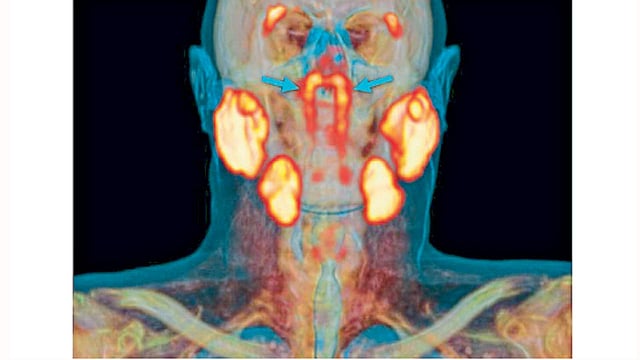

पीएसएमए पेट/सीटी या अत्याधुनिक यंत्राव्दारे कर्करोगाच्या एका रुग्णाचे स्कॅनिंग करत असताना नेदरलँडमधील डॉक्टरांना या नवा अवयवाचा शोध लागला. कर्करोगाच्या गाठी समजण्यासाठी हे स्कॅनिंग करण्यापूर्वी रुग्णाला किरणोत्सारी द्रव असलेले ग्लुकोजचे इंजेक्शन दिले जाते. त्यामुळे कर्करोगाच्या गाठी स्कॅनमध्ये ‘उजळलेल्या’ दिसतात. या स्कॅनमध्ये नासोफरीनॅक्स भागात (मृदूटाळूवरील भाग) आत्तापर्यंत कधीही न दिसलेला भाग दिसून आला. मुख्य लाळग्रंथीच्या बाजूला या दोन नव्या ग्रंथी असल्याचे दिसून आले.

पचनासाठी आपल्याला लाळेची गरज असते. पॅराटॉईड, सबमँडीब्युलर आणि सबलिंग्युलर या ग्रंथींमधून लाळ स्रवते. याशिवाय लाळ स्रवणाऱ्या छोट्या छोट्या हजारभर ग्रंथीही असतात. त्या सर्व आपल्या तोंडामध्ये विखुरलेल्या असतात. सूक्ष्मदर्शकाशिवाय या छोट्या-छोट्या ग्रंथी दिसत नाहीत. नव्याने सापडलेल्या ठळकपणे दिसणाऱ्या चौथ्या ग्रंथी आहेत.  नाकाच्या मागे आणि टाळूच्या वरच्या भागात, मानवी डोक्याच्या मध्याच्या जवळ आहेत.

ॲमस्टरडॅम विद्यापीठातील शल्यचिकित्सक मॅथिज वॉल्स्टार यांच्या नेतृत्वाखालील पथकाने या नव्या ग्रंथींचा अभ्यास केला. नव्या अवयाबाबत ते म्हणाले,` या ग्रंथींच्या स्थानावरून त्यांना ट्युबेरिअल ग्लँड असे त्यांना म्हणता येऊ शकेल.  या साठी १०० रुग्णांची तपासणी करण्यात आली. त्या सर्वांचे पीएसएमए पेट/सीटी स्कॅन करण्यात आले. सर्वांमध्ये या नव्या ग्रंथी आढळून आल्या. तसेच एक महिला व एका पुरुषाची प्रत्यक्ष शारीरिक तपासणी करण्यात  आली त्यातही या पेशी आढळून आल्या. आतापर्यंतच्या वैद्यकीय पाहणीत या ग्रंथी आढळून आल्या नव्हत्या.``